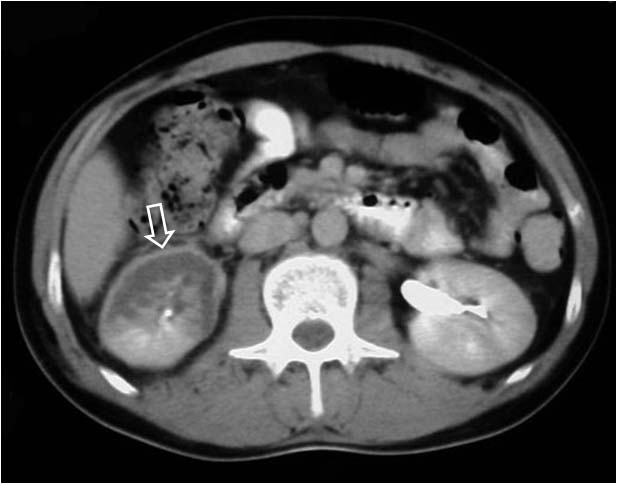

En casos de oclusión de la arteria renal o alguna de sus ramas se produce una ausencia total o parcial del nefrograma. Sin embargo, unas horas después puede verse un fino anillo periférico subcapsular de corteza renal perfundida por colaterales capsulares. Se ha descrito que este signo permite diferenciar el infarto renal de la nefronia lobar, en la que no está presente este signo. También se encuentra en la literatura como Signo del borde cortical.

La imagen corresponde a una TC que muestra este signo (flecha) en el riñón derecho en un paciente con traumatismo renal con lesión del pedículo. La parte posterior del riñón no está afectada y conserva su vascularización.